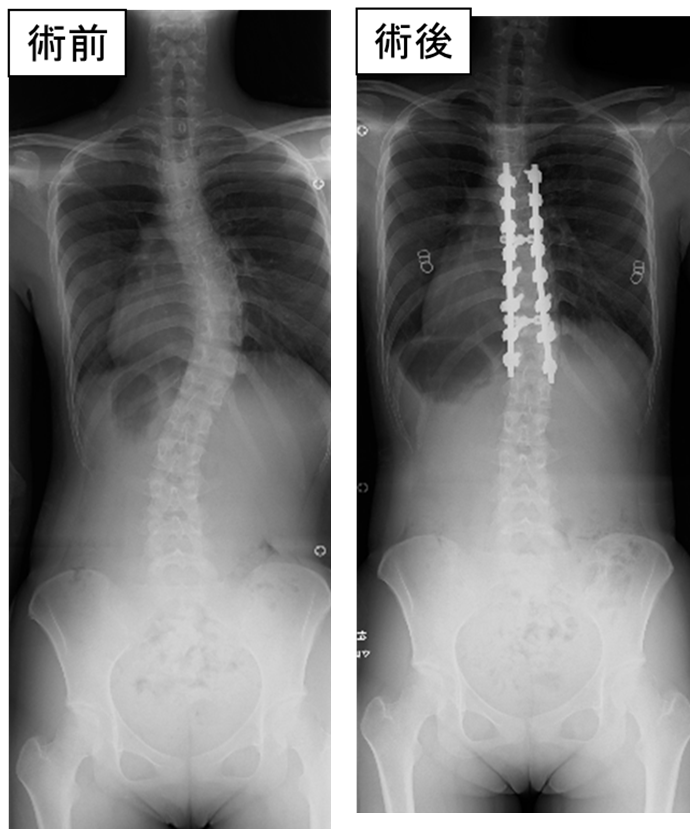

症例数は少ないですが、思春期特発性脊柱側弯症、先天性脊椎側弯症(半椎)、頚胸椎移行部の脱臼骨折症例などでは、CTベースドナビゲーションなどのコンピューター支援技術を使用し安全な手術を行っています。このような症例では背骨(椎体)にスクリューを挿入し矯正します。スクリュー周囲には重要な神経(脊髄・馬尾・神経根など)や血管(胸腹部大動脈・椎骨動脈など)が存在するため、これらを避けて挿入する必要があります。ナビゲーション手術は、術前に撮影したCT画像をコンピューターに取り込み、リアルタイムにどこにスクリューが挿入されているか確認しながら行う手術です。

思春期特発性脊柱側弯症

ナビゲーションを用いてスクリューを椎弓根に挿入し矯正しています。